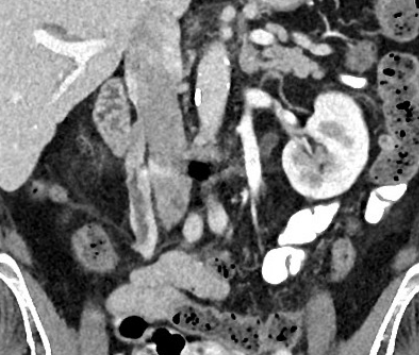

- Thrombophlébite ++

- Douleurs quadrant inférieur (droit++)

- Patientes Post-partum++

- Veine ovariene Droite++